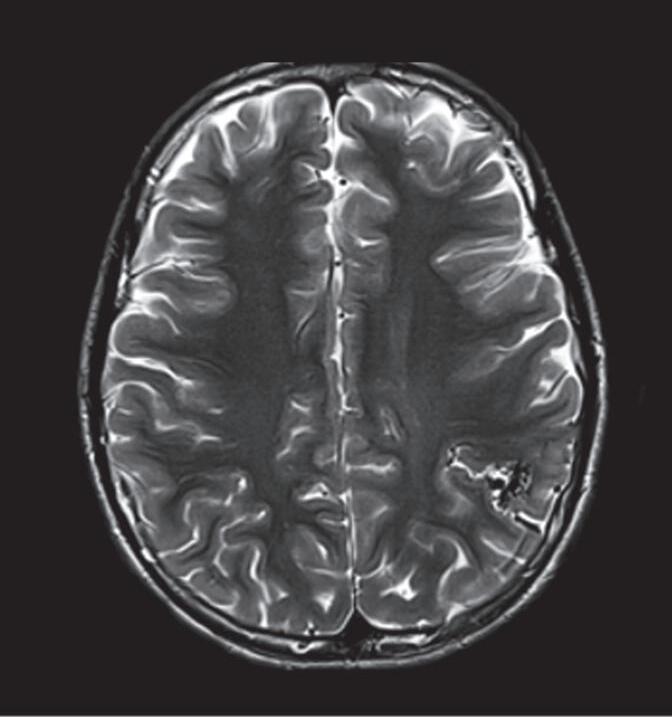

Fig. 1-14. RNM encéfalo, T2 axial (a) e coronal (b), demonstrando MAV grau 2 no lobo parietal esquerdo.

Arteriografia cerebral (c) AP e (d) em perfil, demonstrando a irrigação pelos ramos da artéria cerebral média (ACM) e anterior (ACA), com drenagem pela veia de Labbé, no seio transverso sigmoide.